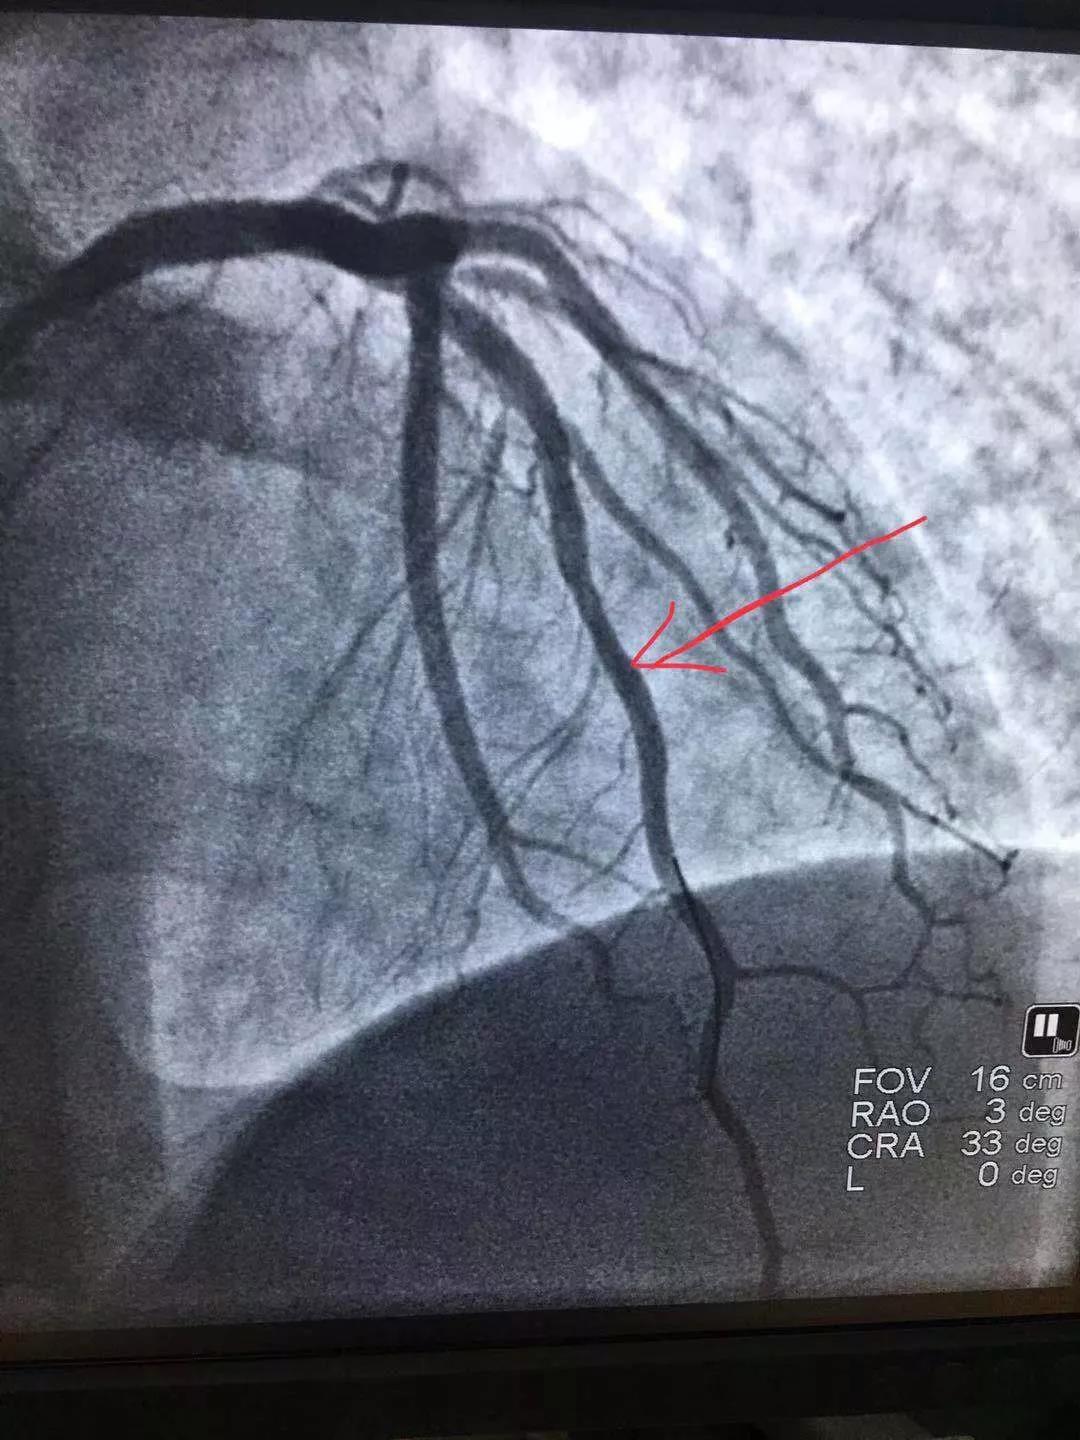

手術(shù)后與手術(shù)前

術(shù)中倫主任、徐遵敬主治醫(yī)師發(fā)現(xiàn)病人心臟前降支冠狀動脈完全閉塞,征求病人同意后馬上植入支架治療。當(dāng)冠狀動脈開通的一煞那,病人胸痛馬上消失,并在手術(shù)臺上發(fā)出了“我不痛了,我舒服了,你們真是再世華佗”的感嘆。術(shù)后病人曾出現(xiàn)頻發(fā)室性早搏,一過性左束支傳導(dǎo)阻滯,經(jīng)嚴(yán)密治療后病情好轉(zhuǎn)穩(wěn)定。